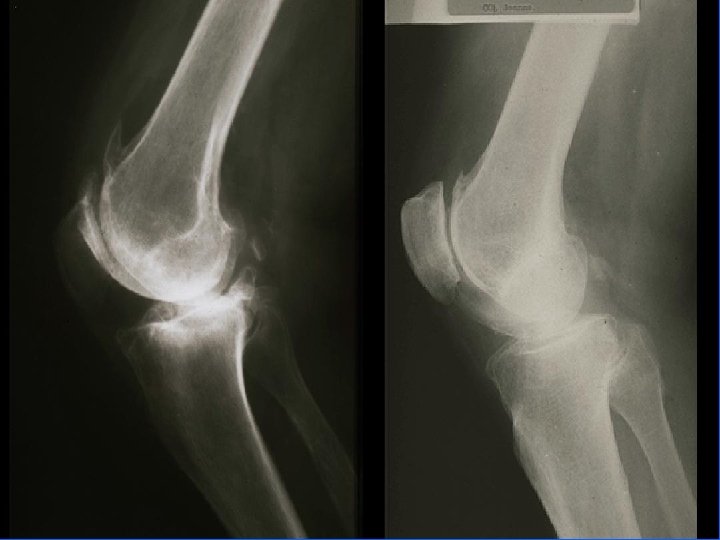

Arthrose fémoro-patellaire Clinique / Iconographie • Douleur à : • L’extension contrariée de la jambe • A la pression de la rotule sur genou fléchi • Au toucher rotulien • A la manœuvre du rabot • Bilan radiographique : articulation fémororotulienne • Incidence axiale 30 ou 60° • Incidence f et P genoux en charge

Arthrose fémoro-tibiale Iconographie • Radiographie : – Face en appui bipodal – Profil – Schuss (face en charge à 30° de flexion) pour compartiment post • Signes: – Pincement interligne – Ostéophytose – Ostéosclérose sous-chondrale avec géodes